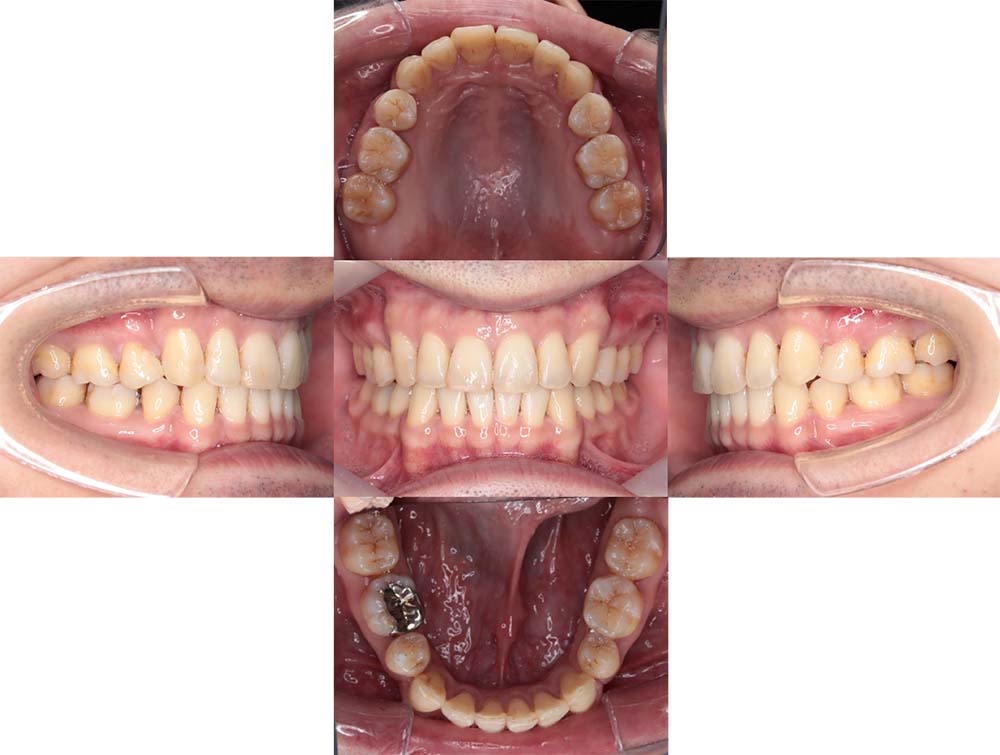

症例21

| 主訴 | 下の前歯がガタガタしている。 |

| 診断名あるいは主な症状 | 叢生、左下第二大臼歯の歯根吸収 |

| 年齢/性別 | 24歳・男性 |

| 矯正ステージ | 大人の矯正治療 |

| 治療方法 | ワイヤー矯正 |

| 抜歯部位/抜歯有無 | 下顎左側第二大臼歯 |

|---|---|

| 治療内容 | 下顎左側第二大臼歯の歯根吸収を認めるため抜歯し親知らずを並べた |

| 費用 |

85万円程度(2025.10時点の料金となります。) ※矯正基本料金、審美ブラケットを含む |

| 治療期間 | 3年5ヶ月 |

| 主なリスク・副作用 | 痛み、歯根吸収、歯肉退縮、虫歯、後戻り |